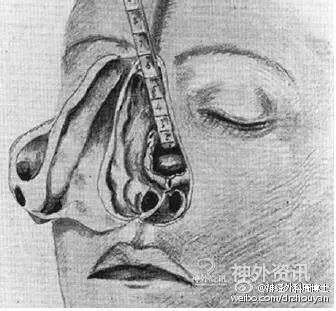

DANDY使用额颞开颅显露鞍区及鞍旁的病变。请注意,广泛的大范围的暴露导致了脑表面不可避免的损伤。20世纪二三十年代,这种大范围的开颅方法是必须的,因为这可以将更多的光线带入深部的手术视野,以利于操作粗大的手术器械。那时,Dandy在做垂体瘤手术时,需要牺牲掉左侧的视神经来获得肿瘤切除时所需要的光线照明。

1897年3月16日,Schloffer的第一台经鼻蝶垂体手术。病人是一个30岁男性,表现有垂体机能减退、视物模糊以及进行性颅内压增高。手术创伤很大,尽管切除了鼻中隔、鼻甲、筛窦气房和左眶内侧壁,可是术中的定位定向仍非常复杂。因而,Schloffer在术前的影像片上测量了从眉间到蝶鞍前侧面的距离,并使用一个量油尺探测手术空间的大小。

Cushing的唇下经鼻中隔入路切除垂体肿瘤。注意观察:头盔式头灯可以显著改善术野深部的照明。